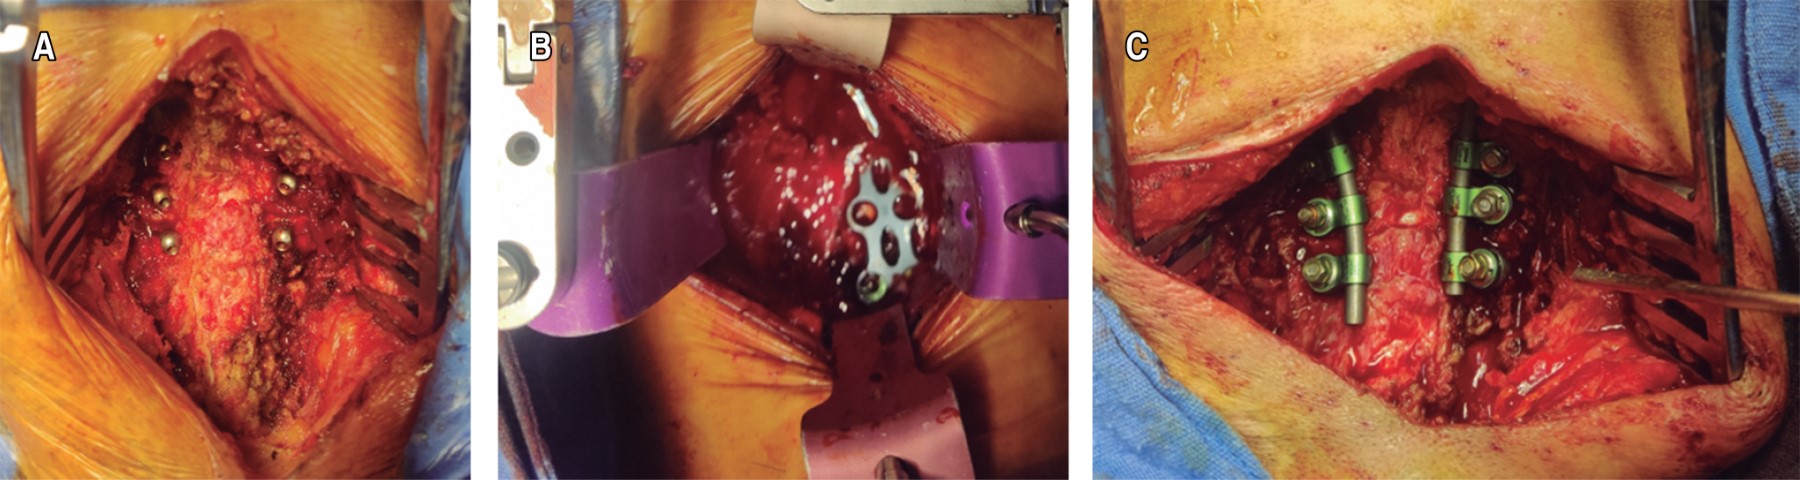

Subaxial cervical spine luxation is a frequent entity in polytraumatized patients, regularly accompanied by neurological injuries such as paraplegia or quadriplegia, requiring urgent surgical treatment in order to stabilize, align and decompress the nerve structures, sometimes it is not possible to perform this type of procedure early due to the general conditions of the patient or the conditions of the hospital units, leading to a late treatment, however, undiagnosed luxation occur, or in the worst case scenario, an inadequately treated injury with poor results that lead to an unsatisfactory evolution of the patient, with chronic pain and neurological deficit. We analyze the case of a patient with subaxial cervical spine luxation, with torpid evolution, requiring a new intervention two years after her injury, performed in three specific sequential times, achieving the patient's recovery and motor functionality.REFERENCES